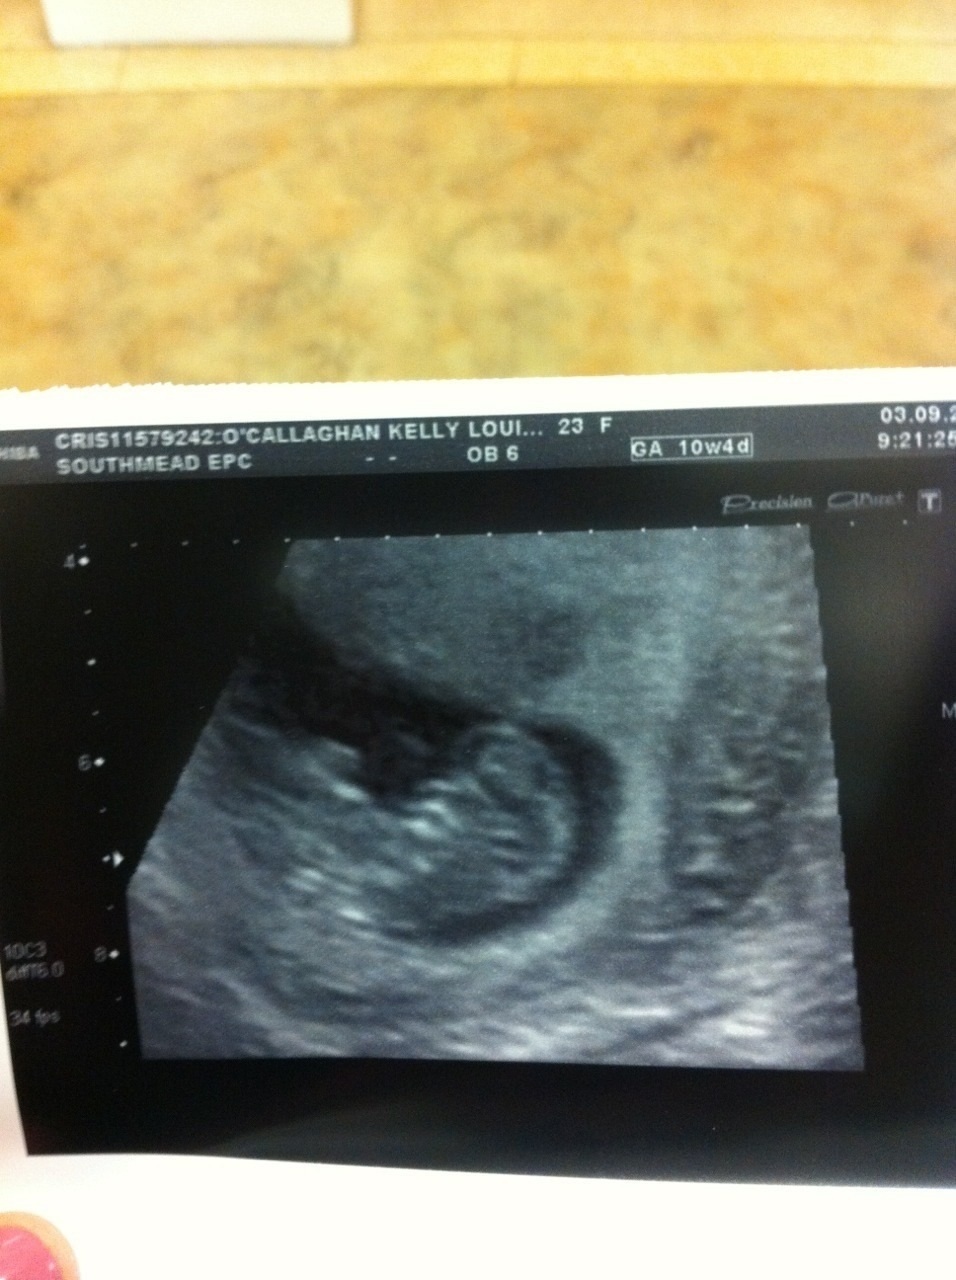

Attachment 13735

Baby looks a little too young here to be able to tell. I think you need a scan around 12-13 weeks in order to be able to guess.

Oh ok ill try again in a few weeks then :-)